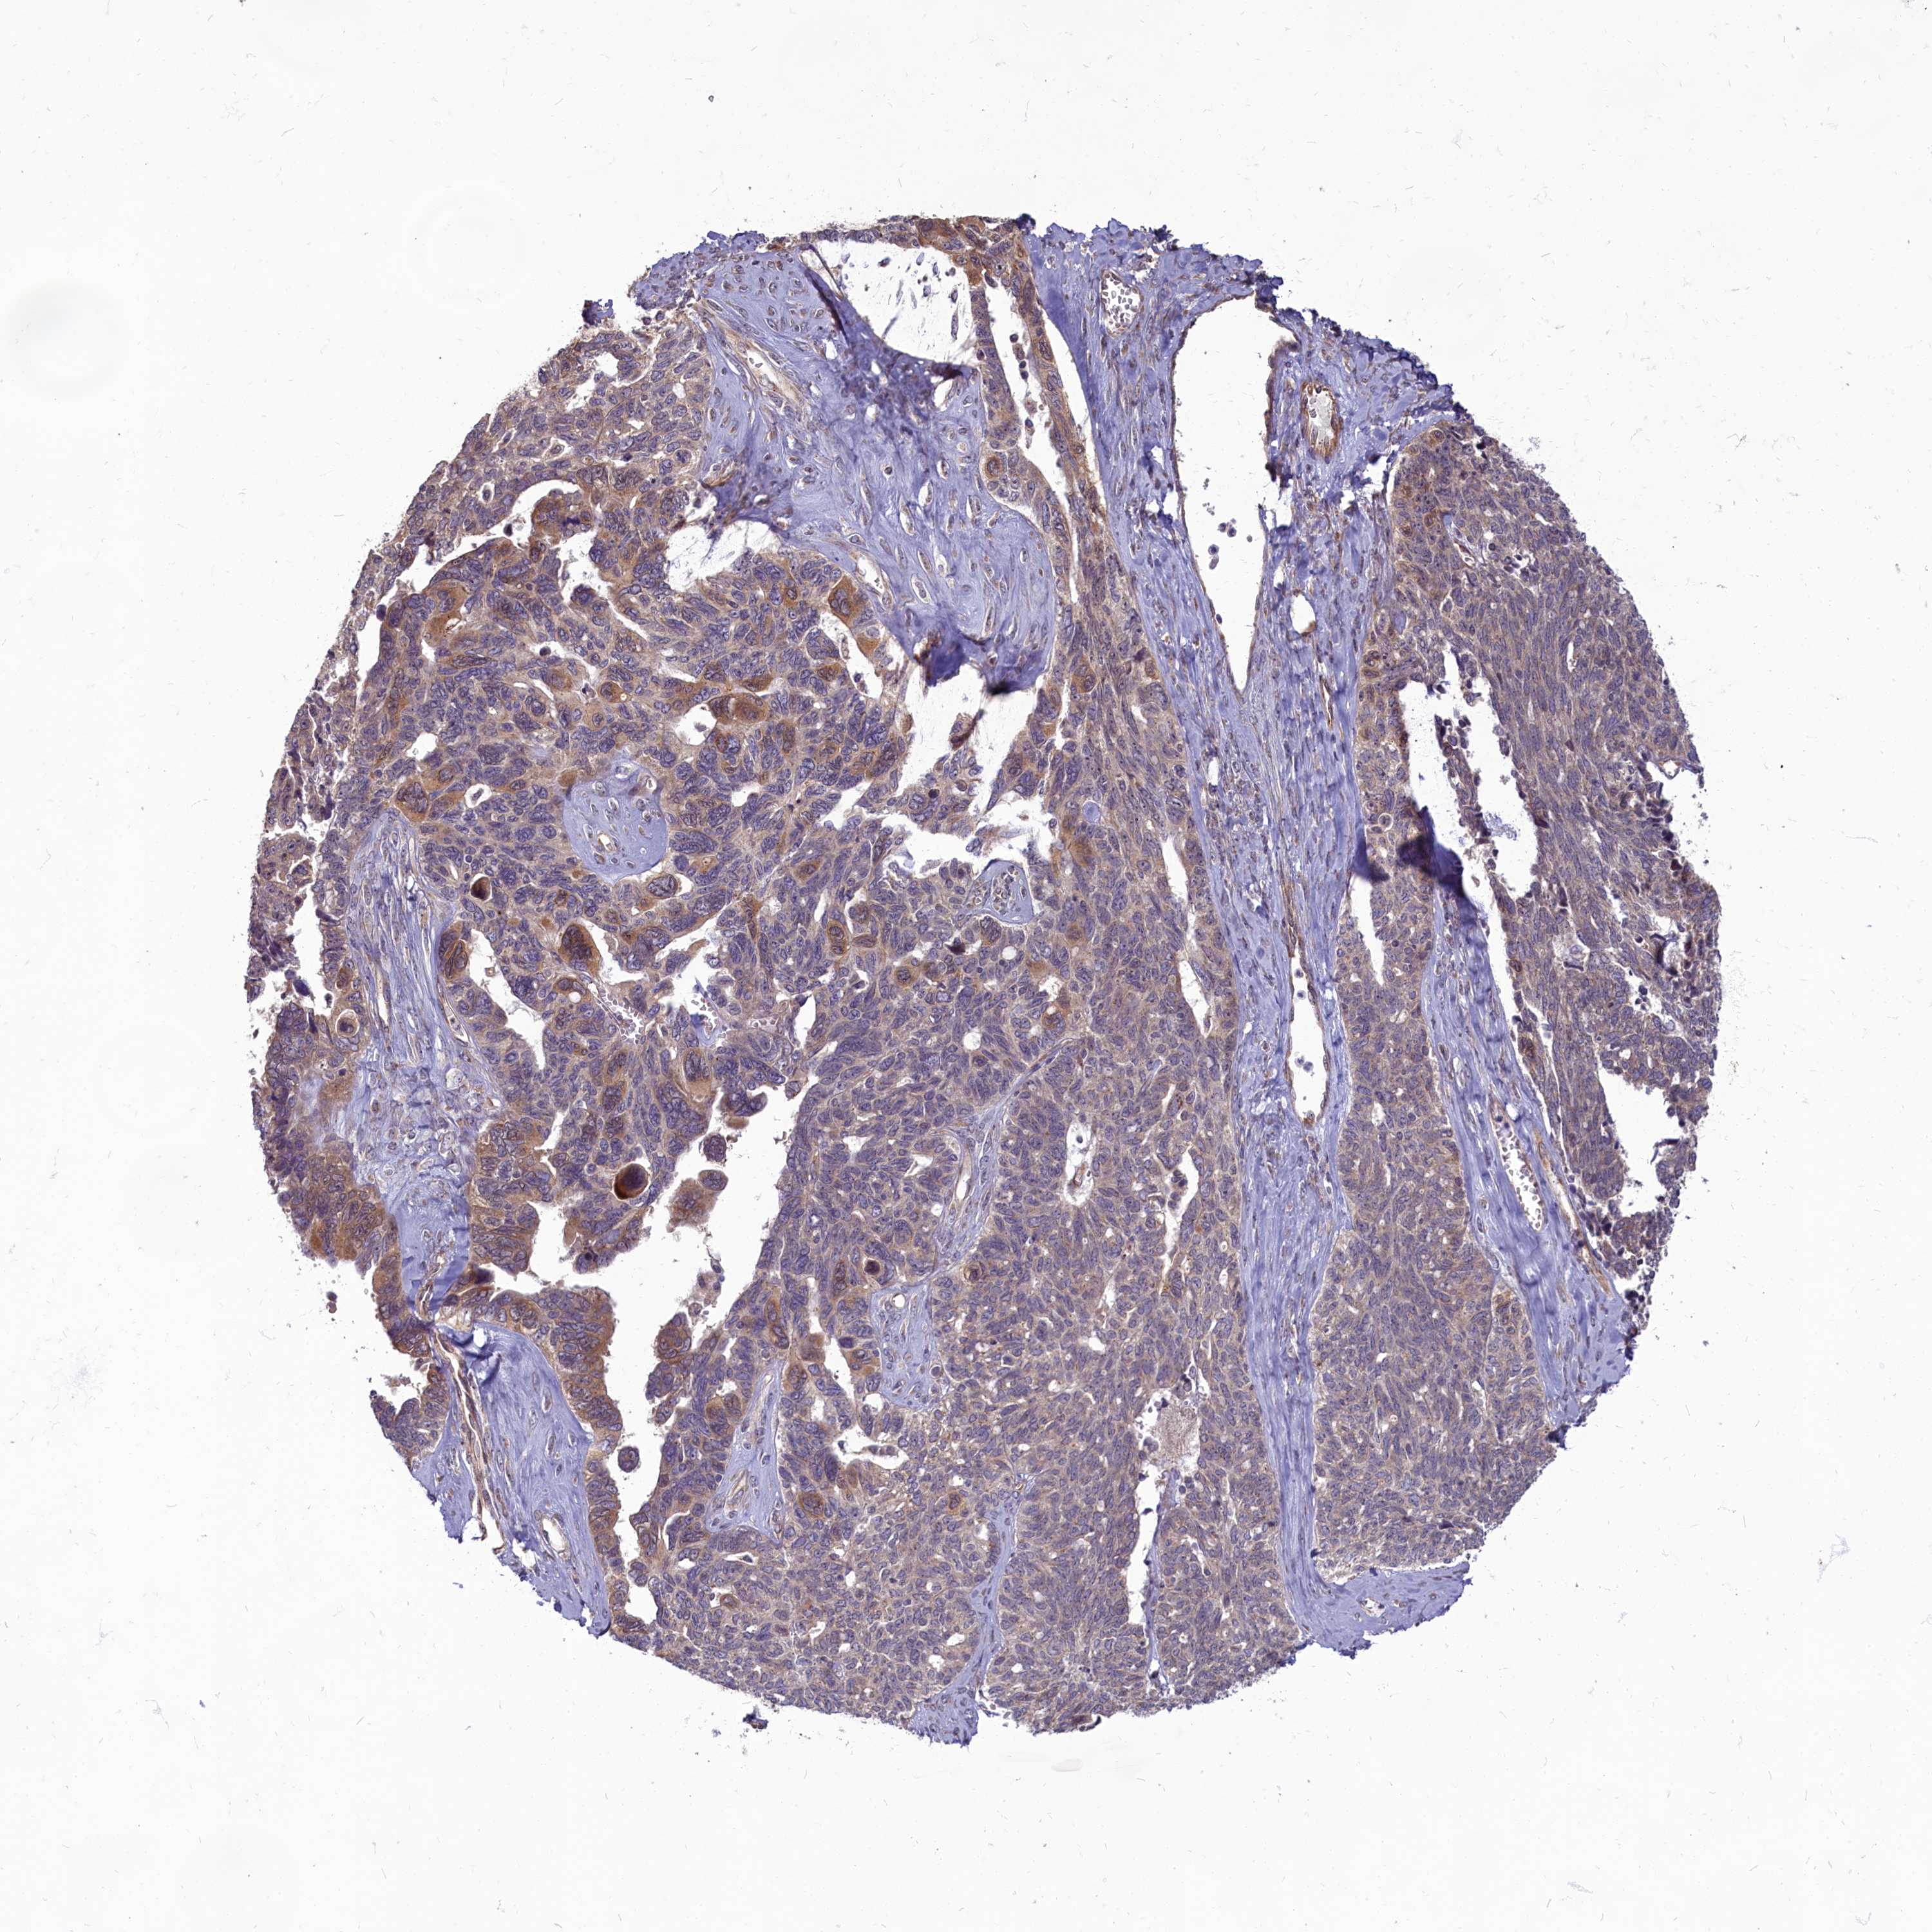

OVARIAN CANCER - Protein expressioni

A mouse-over function shows sample information and annotation data. Click on an image to view it in a full screen mode. Samples can be filtered based on level of antibody staining by selecting one or several of the following categories: high, medium, low and not detected. The assay and annotation is described here.

Note that samples used for immunohistochemistry by the Human Protein Atlas do not correspond to samples in the TCGA dataset.

Antibody stainingi

Antibody staining in the annotated cell types in the current human tissue is reported as not detected, low, medium, or high, based on conventional immunohistochemistry profiling in selected tissues. This score is based on the combination of the staining intensity and fraction of stained cells.

Each image is clickable and will lead to virtual microscopy that enables deeper exploration of all samples and also displays staining intensity scores, fraction scores and subcellular localization as well as patient and tissue information for each sample.

Antibody HPA041188

Staining

High

Medium

Low

Not detected

Intensity

Strong

Moderate

Weak

Negative

Quantity

>75%

75%-25%

<25%

None

Location

Nuclear

Cytoplasmic/membranous

Cytoplasmic/membranous,nuclear

Cystadenocarcinoma, serous, NOS

Carcinoma, endometroid

Cystadenocarcinoma, mucinous, NOS

Carcinoma, NOS